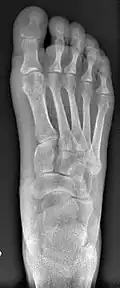

- Second metatarsal stress fracture (Fig. 5)